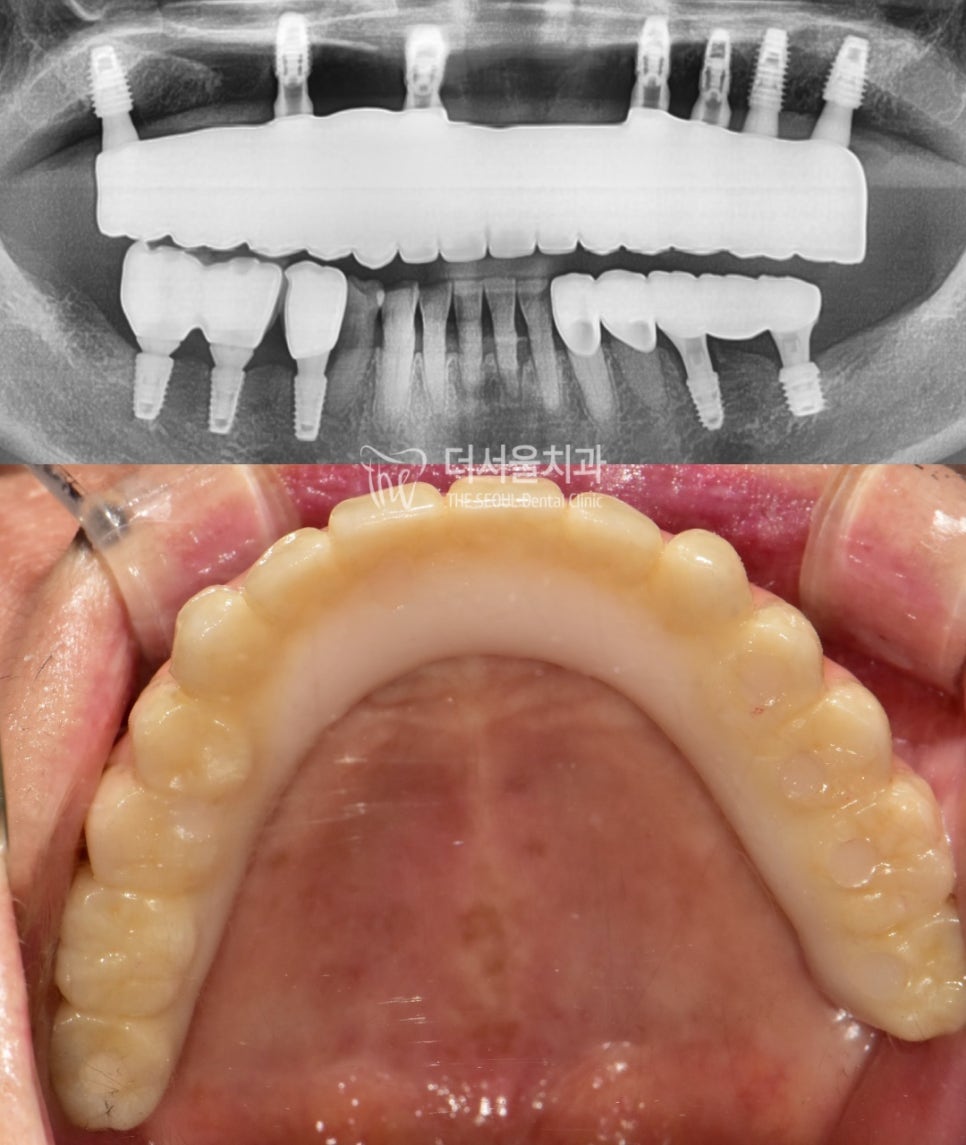

4. 튼튼한 최종 보철

골 유착이 충분히 되었다면

상부에 보철을 올려드릴 건데요,

14개의 자연치 저작기능을

대신해야 되기 때문에

풀아치 타입으로 제작했습니다.

그리고 상악 전체와 하악 어금니를 재건한 만큼

맞닿는 대합치와 원활히 저작할 수 있도록

높이도 잘 체크해 드렸습니다.